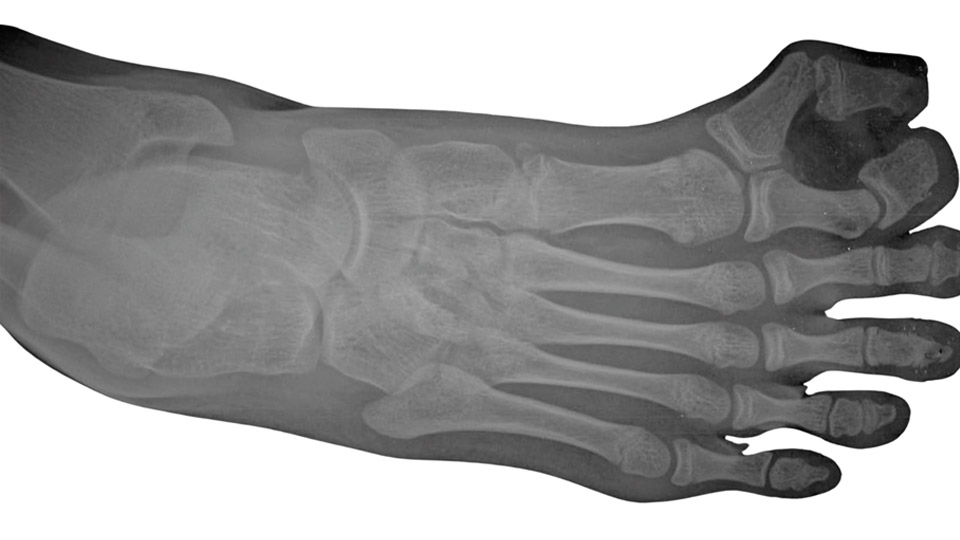

A fizikális vizsgálat során ortopéd szakorvosunk megvizsgálja a láb statikai viszonyait, az ujjak elhelyezkedését, a bőrelváltozásokat, a járáskép esetleges megváltozását. A tapintási vizsgálat során a csontos képletek elmozdíthatóságát, stabilitását és kapcsolódását is értékeljük. A diagnózis megerősítéséhez röntgenfelvétel (RTG) készül a láb elülső és oldalsó nézetéből, szükség esetén kiegészítve ultrahangvizsgálattal vagy MRI-vel, ha az érintett terület ideg- és lágyrészviszonyai részletesebb megítélést igényelnek.

A lábujj eltávolító műtét elsősorban polydactylia (többujjúság) esetén válik szükségessé, amikor a lábon az átlagos öt ujj helyett hat vagy annál több lábujj fejlődik ki. Ez az állapot leggyakrabban a születés során már észlelhető, és lehet önálló fejlődési rendellenesség vagy része egy komplexebb genetikai szindrómának. A többletujj elhelyezkedhet mediálisan (a hallux, azaz nagylábujj felé), laterálisan (a kisujj irányában) vagy interkalált módon (a meglévő ujjak között). Az extra ujj felépítése változó lehet: tartalmazhat teljes csontos vázat (ossificatio), ízületet (articulatio), inakat (tendines), idegeket (nervi) és körömlemezt (unguis), vagy csak lágyrészt.